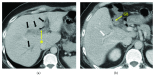

Pylephlebitis is defined as a septic thrombophlebitis of the portal vein and its tributaries that is associated with multiple suppurative abdominal infections. We report a case of pylephlebitis associated with a cholecystocolonic fistula (CCF). A 41-year-old man presented with upper abdominal pain and anorexia for 1 month. Abdominal contrast-enhanced computed tomography (CT) revealed thrombosis in the left and anterior branch of the portal vein and thickening of the walls of the portal vein and periside portals. The gallbladder was collapsed and pneumobilia was seen in the biliary tract. Blood culture was positive for Streptococcus anginosus. A diagnosis of thrombophlebitis of the portal vein associated with CCF was made, and the patient was immediately managed with an intravenous broad-spectrum antibiotic and anticoagulation. After the portal vein thrombosis (PVT) propagation and inflammation had subsided, cholecystectomy and partial resection of the transverse colon were performed. Pylephlebitis is rare but is a life-threatening complication of intra-abdominal infection. A high index of suspicion is required, and a CT scan should be performed immediately for an early diagnosis and appropriate treatment.